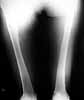

At present the problems to be dealt with were: coxa vara and femoral shortening (5cm) on the right side (Standing radiographs shown in pictures 02,03 and 04).